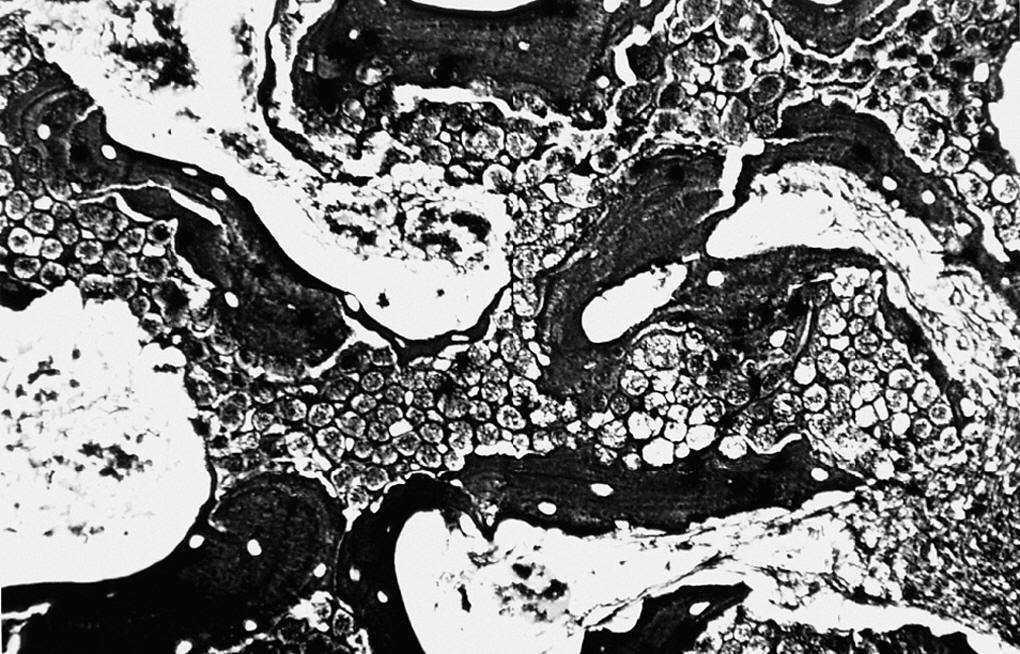

Los poros del implante se observaron parcialmente ocupados por tejido de granulación joven, constituido por numerosas yemas endoteliales y vasos sanguíneos de calibre capilar, así como abundantes células mesenquimales de morfología irregular de citoplasmas amplios, y numerosos fibroblastos dispuestos al azar en el seno de abundante sustancia fundamental. Las fibras colágenas se disponían de forma irregular y frecuentes macrófagos y linfocitos dispersos (fig. 2).

Figura 2. Tejido de granulación que ocupa los poros de la espuma (*) y trabéculas óseas (↑) (zona derecha) (HE, 312,5 x).

Las imágenes de MEB concuerdan con las de microscopia óptica, destacando en la cortical la costra fibrino-hemática. Por debajo de la cortical y rodeando al implante observamos tejido de granulación formado por fibras y abundante celularidad que ocupaba parcialmente los poros (fig. 3).

Figura 3. Población celular de aspecto osteoblástico rellenando los poros (750 x).